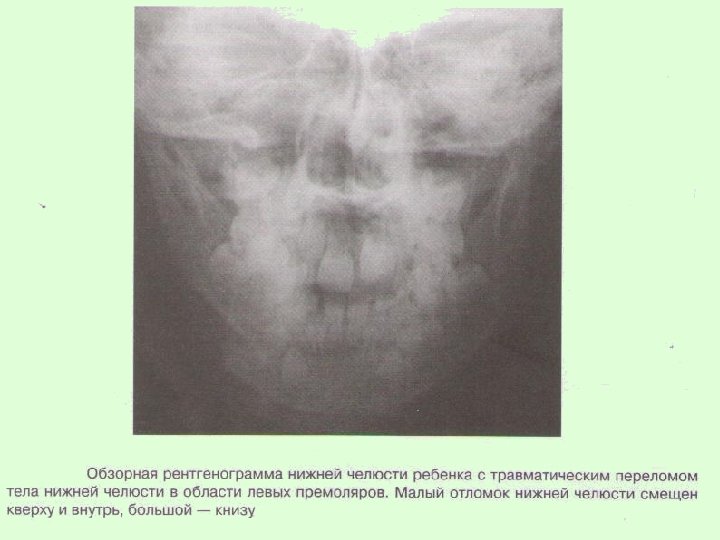

Заключительный диагноз перелома нижней челюсти ставят после проведения рентгенологического исследования в боковой укладке по Генишу или обзорной рентгенограммы нижней челюсти в прямой проекции, при переломе суставного отростка – ортопантомограммы или рентгенограммы сустава по Шуллеру или Парма.

На рентгенограммах обычно определяется нарушение целостности костной ткани, наличие линии перелома, смещение отломков челюсти. В сложных диагностических случаях переломов суставного отростка нижней челюсти у детей для постановки окончательного диагноза при отсутствии явных клинических и рентгенологических признаков используют метод спиральной компьютерной томографии с мультипланарной реконструкцией.